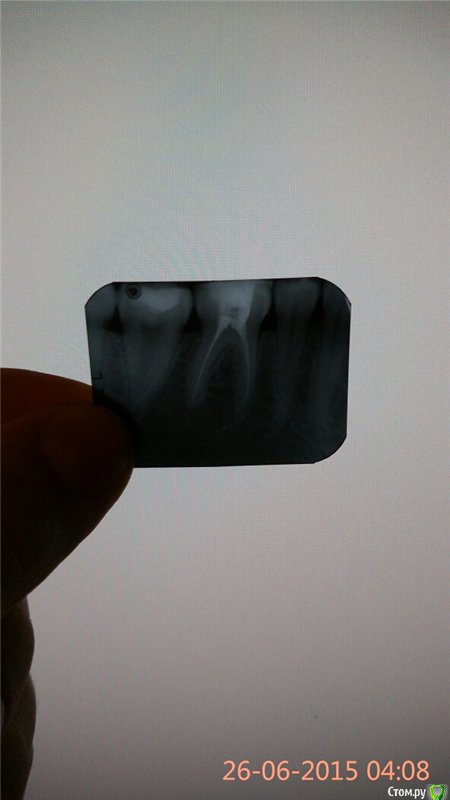

aleksei_sataev Опубликовано 26 июня, 2015 Автор Поделиться Опубликовано 26 июня, 2015 (изменено) Доброго времени суток, доктор удалил нервы ибо зуб сильно разболелся. Прошло чуть более суток после лечения, пока стоит временная пломба. После удаления нервов болит зуб при накусывании и при сжимании челюсти. 1.Прокомментируйте снимок пожалуйста2.И должен ли зуб болеть в первые два дня после пломбирования каналов.Огромнейшее всем спасибо. Изменено 26 июня, 2015 пользователем aleksei_sataev Ссылка на комментарий

aleksei_sataev Опубликовано 26 июня, 2015 Автор Поделиться Опубликовано 26 июня, 2015 (изменено) Еще один ракурс: Изменено 26 июня, 2015 пользователем aleksei_sataev Ссылка на комментарий

anvladd Опубликовано 26 июня, 2015 Поделиться Опубликовано 26 июня, 2015 (изменено) Как так выписку не дали? Судя по снимку каналы пройдены но расширены не очень,хотя если пломбировали методом одного штифта(что не есть хорошо,может в клинике где вы лечитесь по другому не делают,не в коем случае не пытаюсь выступить против доктора,все мы работаем в разных условиях)то норм. Изменено 26 июня, 2015 пользователем anvladd Ссылка на комментарий

aleksei_sataev Опубликовано 26 июня, 2015 Автор Поделиться Опубликовано 26 июня, 2015 Как так выписку не дали? Судя по снимку каналы пройдены но расширены не очень,хотя если пломбировали методом одного штифта(что не есть хорошо,может в клинике где вы лечитесь по другому не делают,не в коем случае не пытаюсь выступить против доктора,все мы работаем в разных условиях)Я не очень понимаю стоматологической терминологии. Обезболивание было ультракаин, соседний зуб пломбировали материалом Filtek, на данном зубе пока временная пломба. Каналы лечили промывали лекарством, вставляли провод от прибора что-то измеряли, в общей сложности чуть более одного часа делали. Канал расширяли. Зуб переделывать надо? Ссылка на комментарий